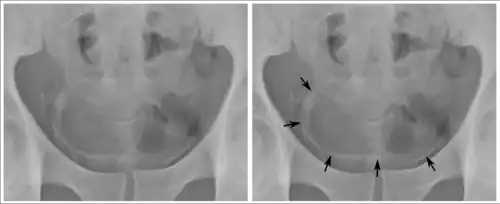

Investigations performed usually include collecting a sample of urine for an inspection for malignant cells under a microscope, called cytology, as well as medical imaging by a CT urogram or ultrasound.[33] If a concerning lesion is seen, a flexible camera may be inserted into the bladder, called cystoscopy, in order to view the lesion and take a biopsy, and a CT scan will be performed of other body parts (a CT scan of the chest, abdomen and pelvis) to look for additional metastatic lesions.[33]

Some forms of medical imaging exist to visualise the bladder. A bladder ultrasound may be conducted to view how much urine is within the bladder, indicating urinary retention. A urinary tract ultrasound, conducted by a more trained operator, may be conducted to view whether there are stones, tumours or sites of obstruction within the bladder and urinary tract. A CT scan may also be ordered.